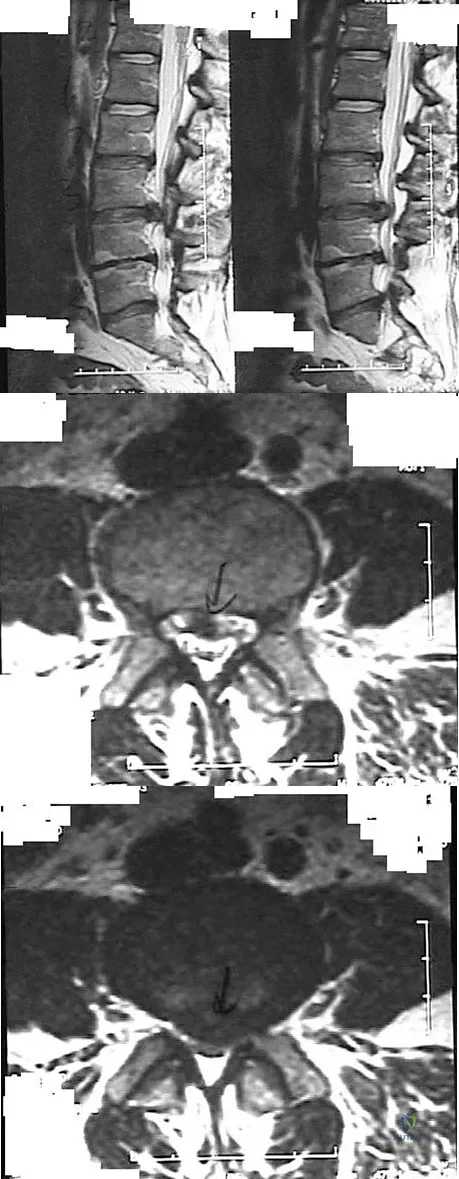

Explanation

Question 61

Figures 28a through 28c show the MRI scans of a 30-year-old woman who weighs 290 lb and has low back and left leg pain. She also reports frequent urinary dribbling, which her gynecologist has advised her may be related to obesity. Examination will most likely reveal

Explanation